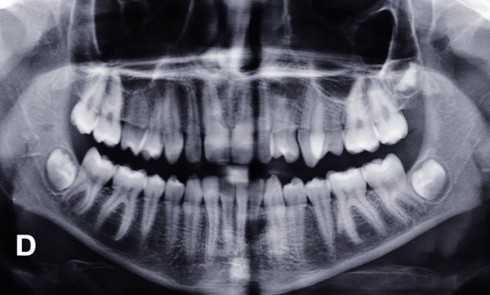

Article réservé à nos abonnés Traitement d’un édentement unitaire antérieur

Depuis quelques années, la dentisterie prothétique et restauratrice s’inscrit dans un schéma d’économie tissulaire maximale par l’intermédiaire de la dentisterie...